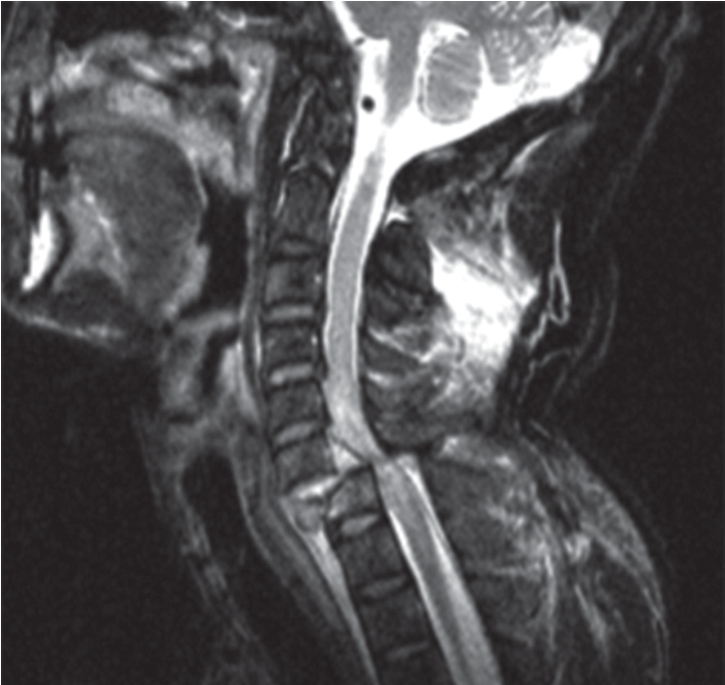

3.脊柱MRI影像 脊椎骨性结构的皮质骨及韧带在T1WI和T2WI上均表现为黑影的低信号;椎间盘在T1WI上不能区分纤维环和髓核,在T2WI上纤维环表现为黑影的低信号,而髓核则为白影的高信号;正中矢状面T1WI上脊髓呈带状灰影的中等信号,边缘光滑、信号均匀,位于椎管中心部位,其前后为低信号的脑脊液;T2WI上脊髓仍为中等信号,其前后的脑脊液呈白影的高信号。横断面上可清楚显示脊髓、脊神经及其与周围的关系(图7-2-8)。

图7-2-8 正常脊椎MRI影像